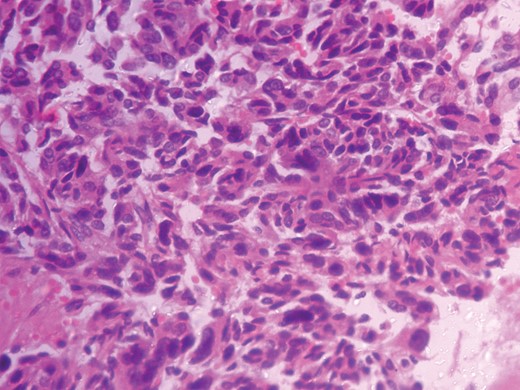

Histopathological analysis reported a well-encapsulated cellular lesion composed of sheets, cords and trabeculae of round to oval epithelial cells with abundant eosinophilic cytoplasm and vesicular nuclei showing Grade 1–2 pleomorphism. Foci of bizarre-looking cells with frequent mitotic figures (1–2/10 HPF) seen. Focal areas of capsular invasion were seen without vascular invasion. A histopathological study indicated ACC (Figs 7 and 8).